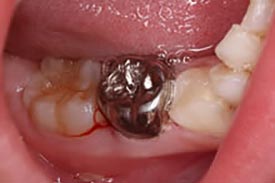

▲虫歯を取って、神経を取って、薬を詰める様子

▲薬を詰めた後の写真(乳歯の奥歯)